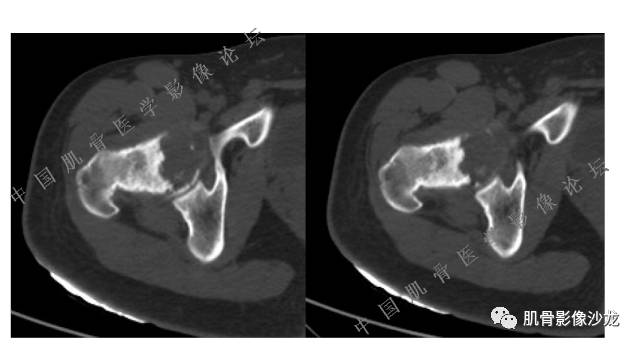

主诉:左髋疼痛1月余

现病史:患者1月余前无明显诱因出现左髋部疼痛,无明显活动受限,当地医院行X线检查,提示左股骨颈异常密度。遂来我院就诊。

既往史:曾患乙型肝炎,未正规治疗,目前无症状。

葛英霖 20:5 4 常规纤维类的多一些,冠状位没有看到明显脂肪。纤维结构不良、纤维组织细胞瘤、软粘纤之类。

夏威夷的风 20:55 大方向纤维类病变

夏威夷的风 20:58 强化渐进性强化吧 边界清晰 里面也见线状低信号

飞鹰行动 21:01 良性纤维组织细胞瘤内部可以有少量脂肪

X(CT、MR)战警 21:01 泡沫细胞被吞噬后形成脂肪信号, bfh可以有脂肪条带样改变

Echo 21:04 总之这例就是各位老师说的硬化边明显,没有软组织肿块,没有侵犯,考虑良性病变,增强渐进性强化,所以考虑BFH